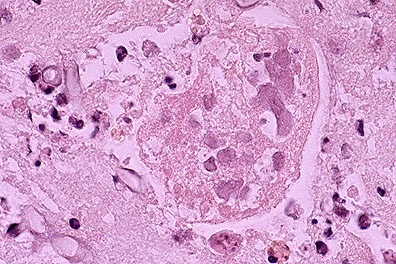

Bronchopneumonia in a raccoon (Procyon lotor) infected with canine morbillivirus. Note the prominent intracytoplasmic inclusions within bronchiolar epithelium and occasionally within macrophages in the bronchiole lumen, and the presence of metastrongyle larva. (HE, 400X, 122K)

Lung: Numerous neutrophils fill alveoli and bronchi. There is abundant necrosis and numerous intraepithelial eosinophilic cytoplasmic inclusions. There are multiple larval and adult nematode cross sections within a bronchus, along with associated neutrophils, eosinophils, macrophages and occasional multinucleated cells.

1. Lung: Pneumonia, bronchointerstitial, subacute, diffuse, moderate, with type II pneumocyte hyperplasia, syncytial cells, and eosinophilic intranuclear and intracytoplasmic inclusion bodies, raccoon (Procyon lotor), procyonid, etiology consistent with canine distemper virus.

2. Lung: Bronchitis and bronchiolitis, suppurative and eosinophilic, multifocal, moderate, with intraluminal adult and larval metastrongyle nematodes.